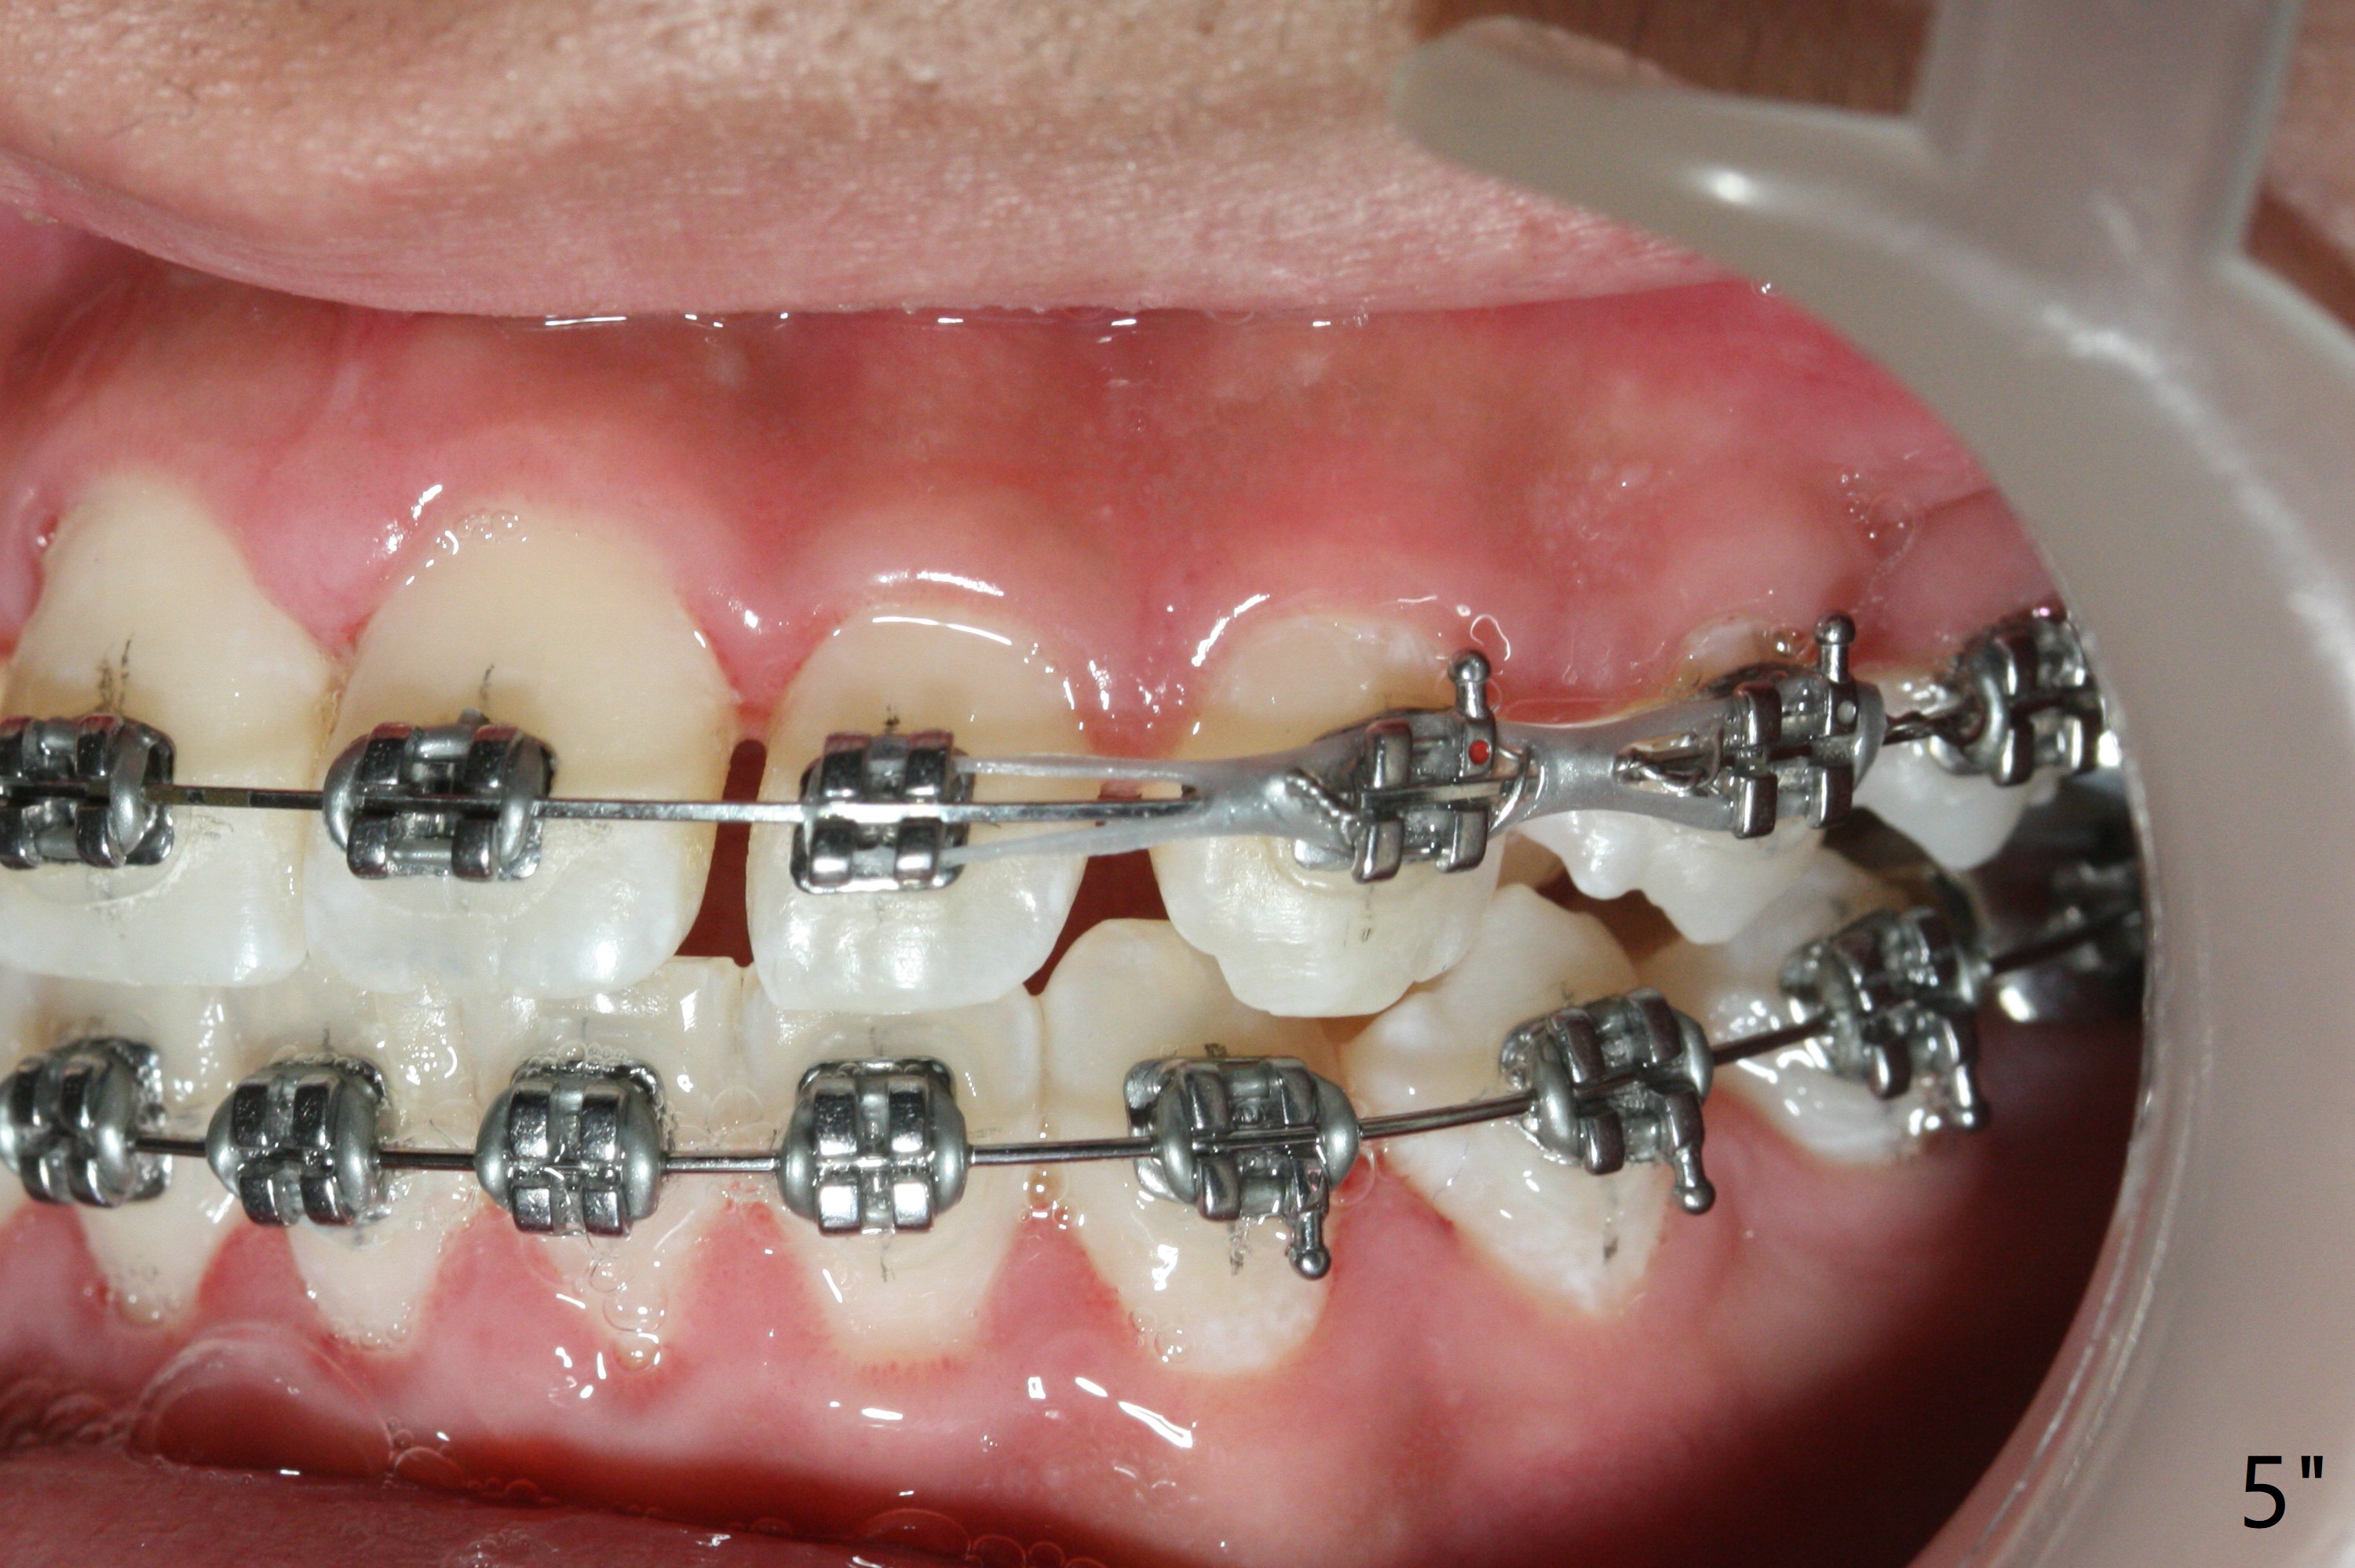

A 15-year-old man finishes orthodontic treatment for congenital missing lateral in 13 months. Molar Class I relationship remains the same (Fig.1,2,4,5). The upper diastemata mesial to 4s (Fig.4,7") close with correction of the upper midline deviation (Fig.2'-4'). The kid is unpleased with the elongated UR1 (Fig.2',3'). In fact it is a preexisting condition (Fig.2 arrow, 2"), but bracket placement at UR1 should have been overcorrected (incisal placement, Fig.3"). The intrusion should be done (Fig.4") before closure of the diastemata, since anchorage may be weakened when the separation between UR1 and 3 increases by using open coil spring. To prevent immediate relapse of the diastema between the upper central incisors, a fixed retainer is placed lingual before debracketing (Fig.6,6',6").